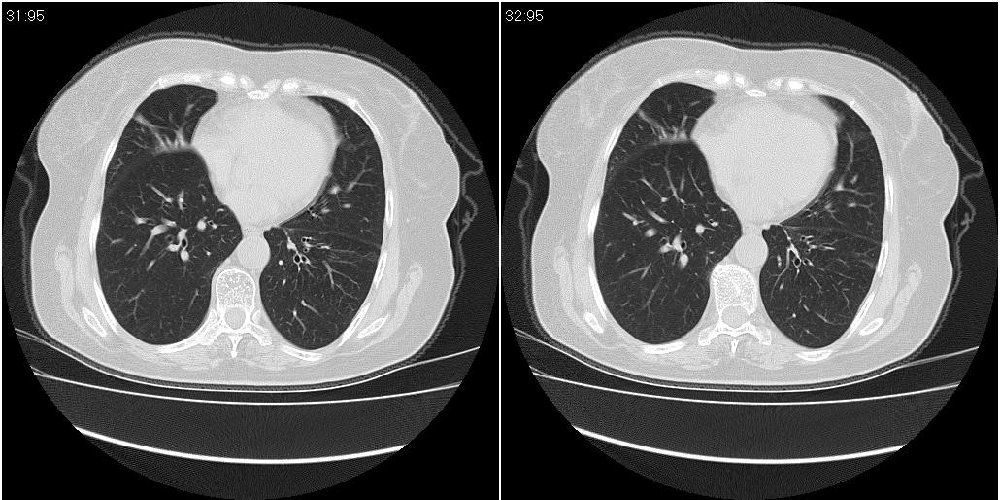

女性,72岁。去年9月份发现肺部病变,诊为肺结核并进行正规治疗至今,但复查后发现ct表现几乎没有变化。

右中间段支气管局限性狭窄,右中叶支气管亦稍显狭窄,但并未见明显占位表现,半年多了,无变化也许是好事,可能为炎性狭窄,建议继续随访。

双肺继发型tb并右中叶内膜tb,轻度支扩,左下胸膜肥厚粘连。

右中间段支气管局限性狭窄,右中叶支气管亦稍显狭窄.

双肺继发性肺结核并右肺中叶节段性肺不张,左下胸膜肥厚粘连。

右肺中叶节段性肺不张,考虑结核或慢性炎症,建议做纤支镜检查。